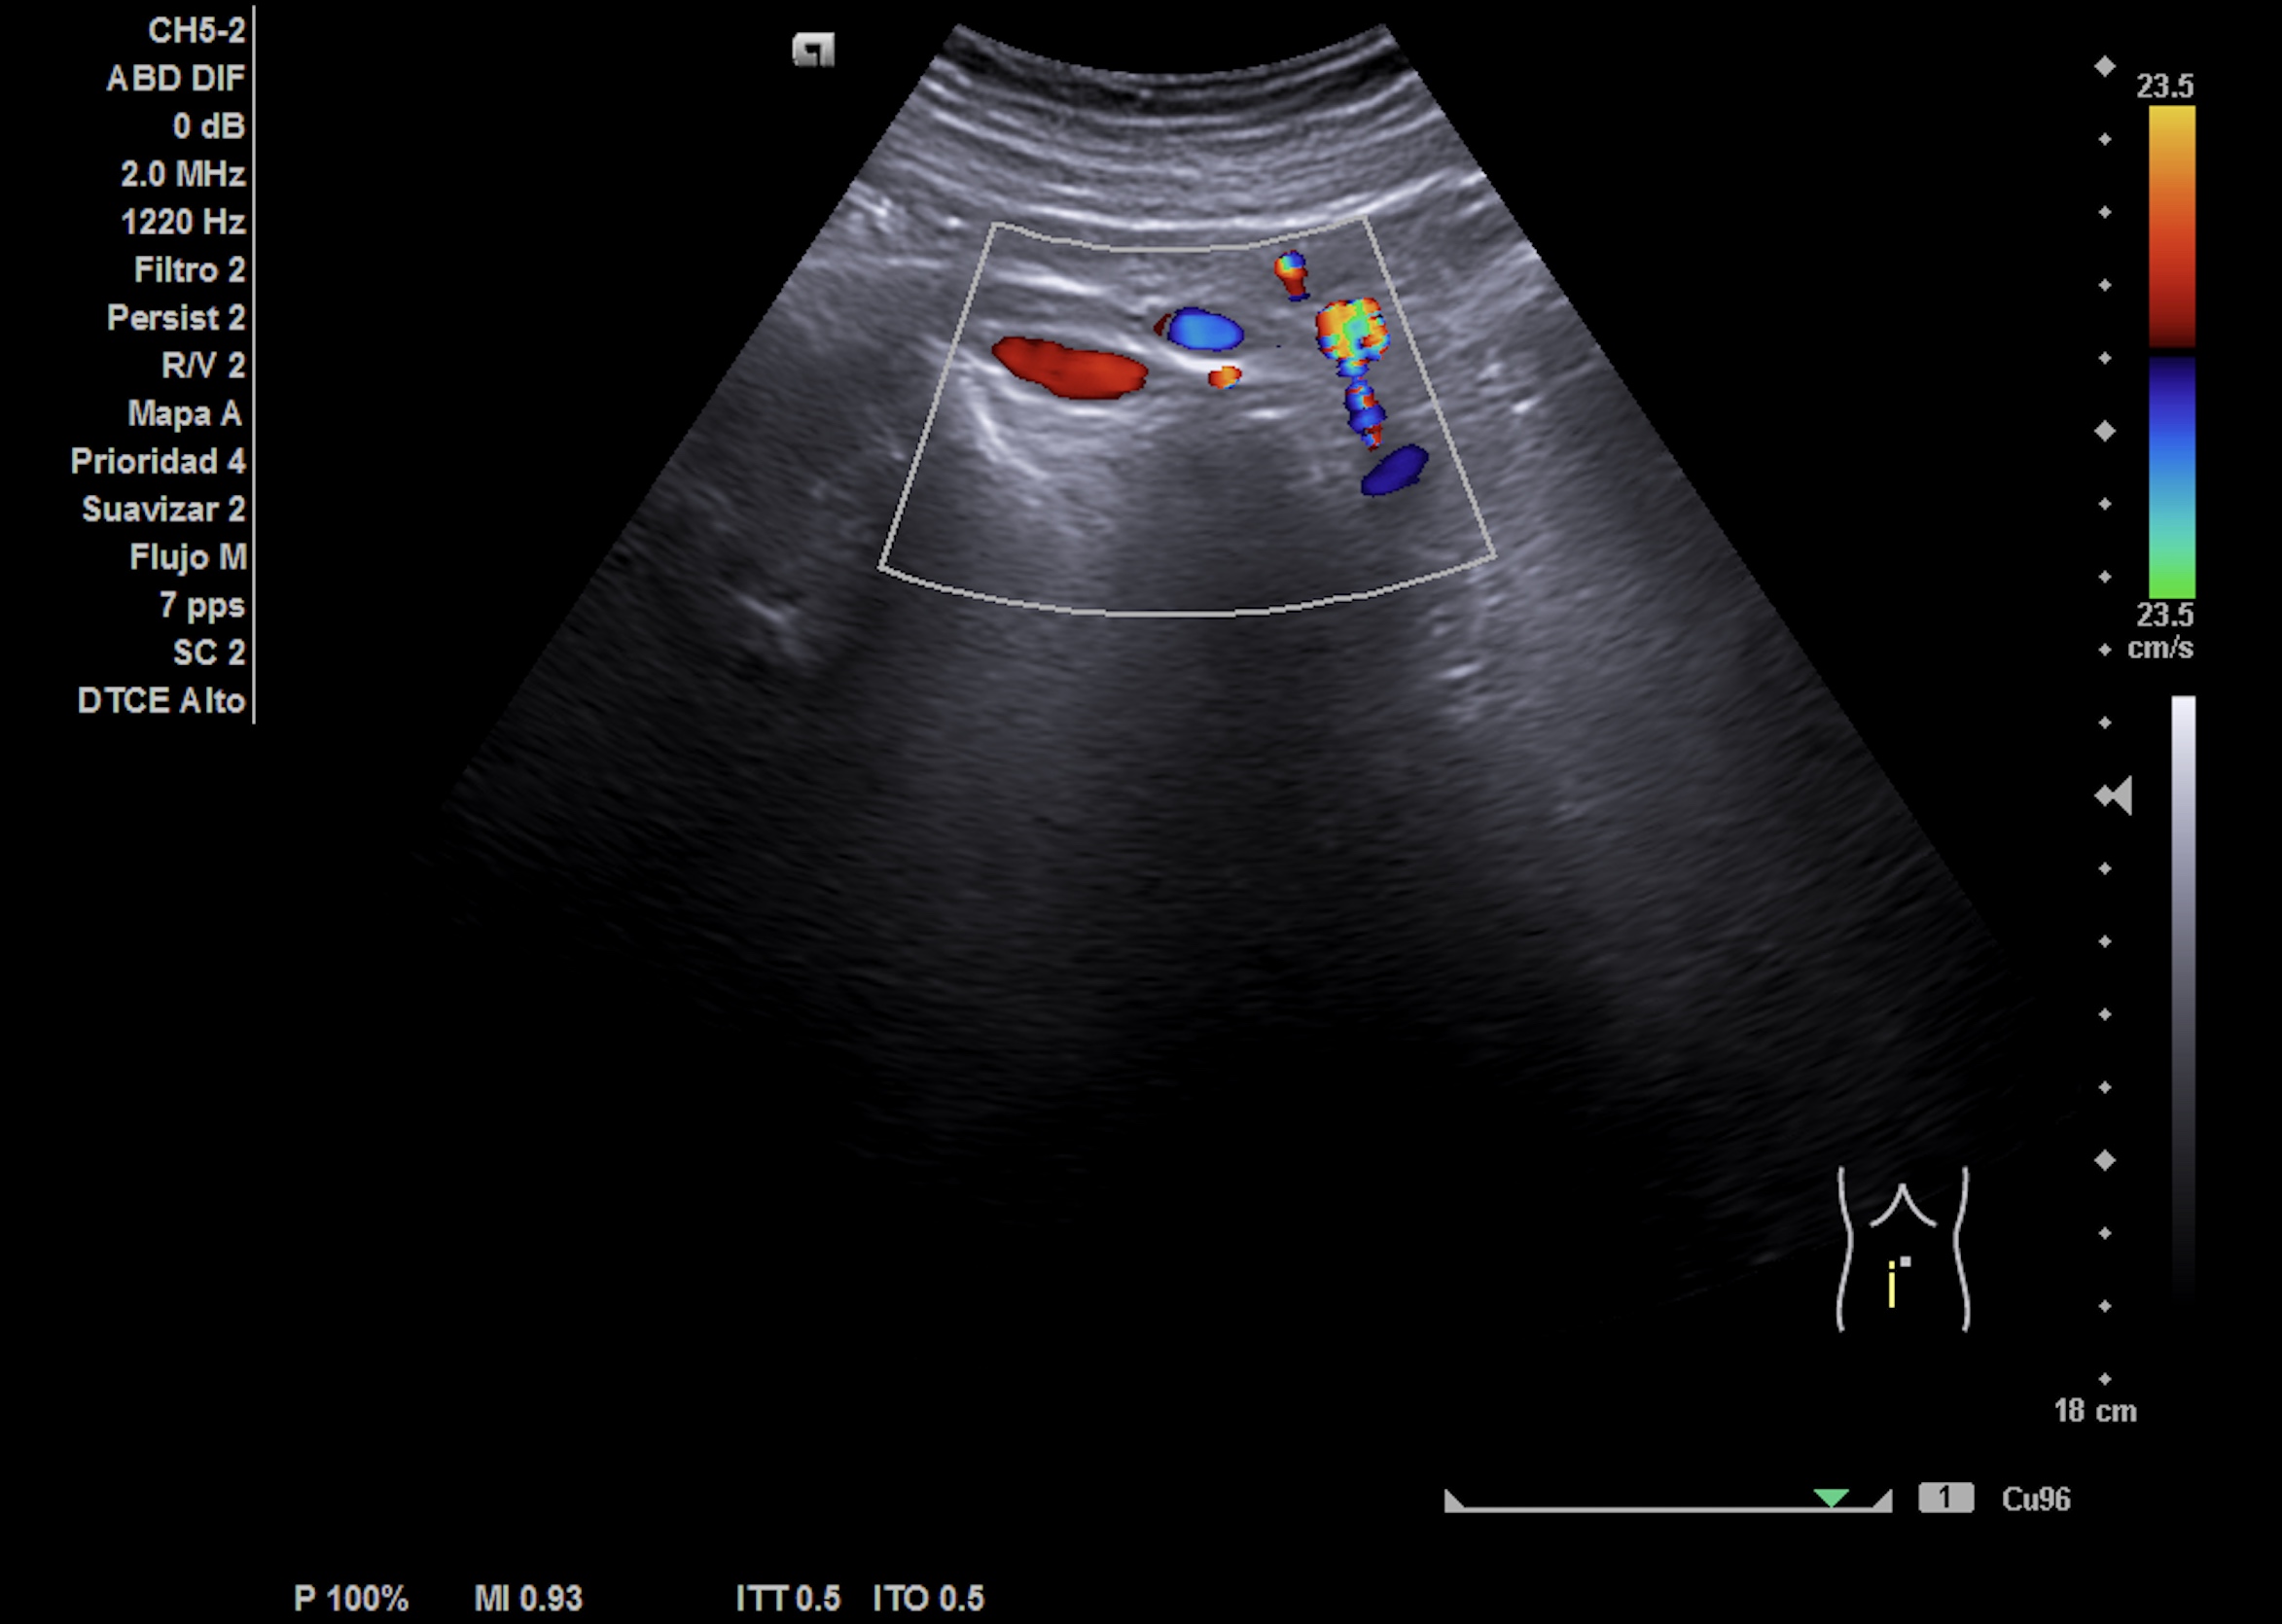

Nueva ecografía clínica renal, vías urinarias y vejiga (a la semana): hidronefrosis grado II que no presentaba hace 1 semana, no nefrolitiasis en cálices renales. Jet ureteral dcho permeable, en zona intermedia de uréter dcho presenta cálculo de 8 mm enclavado en el cruce de los vasos ilíacos con uréter.

Ecografía abdominopélvica urgencias hospital: Ureterohidronefrosis grado II derecha secundaria a litiasis de 7 mm en el uréter medio. Quiste cortical simple de 2.6 cm en el polo inferior.